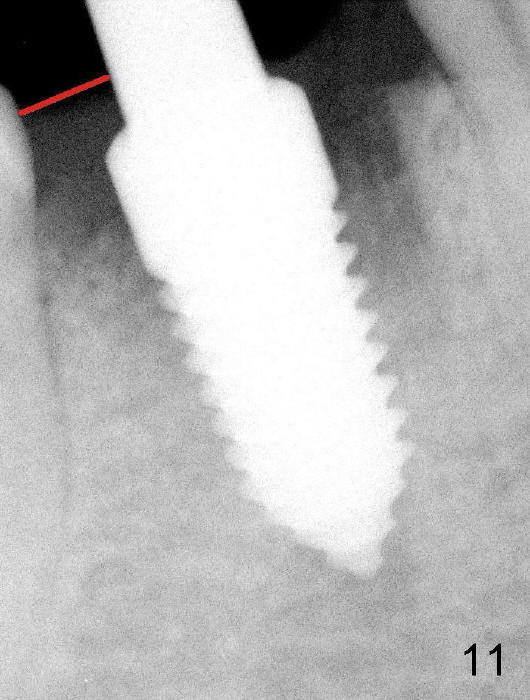

Fig.11: immediately post implantation (6x14 mm one piece). Fig.15: increased bone density in the mesial and distal sockets 3.5 months postop.